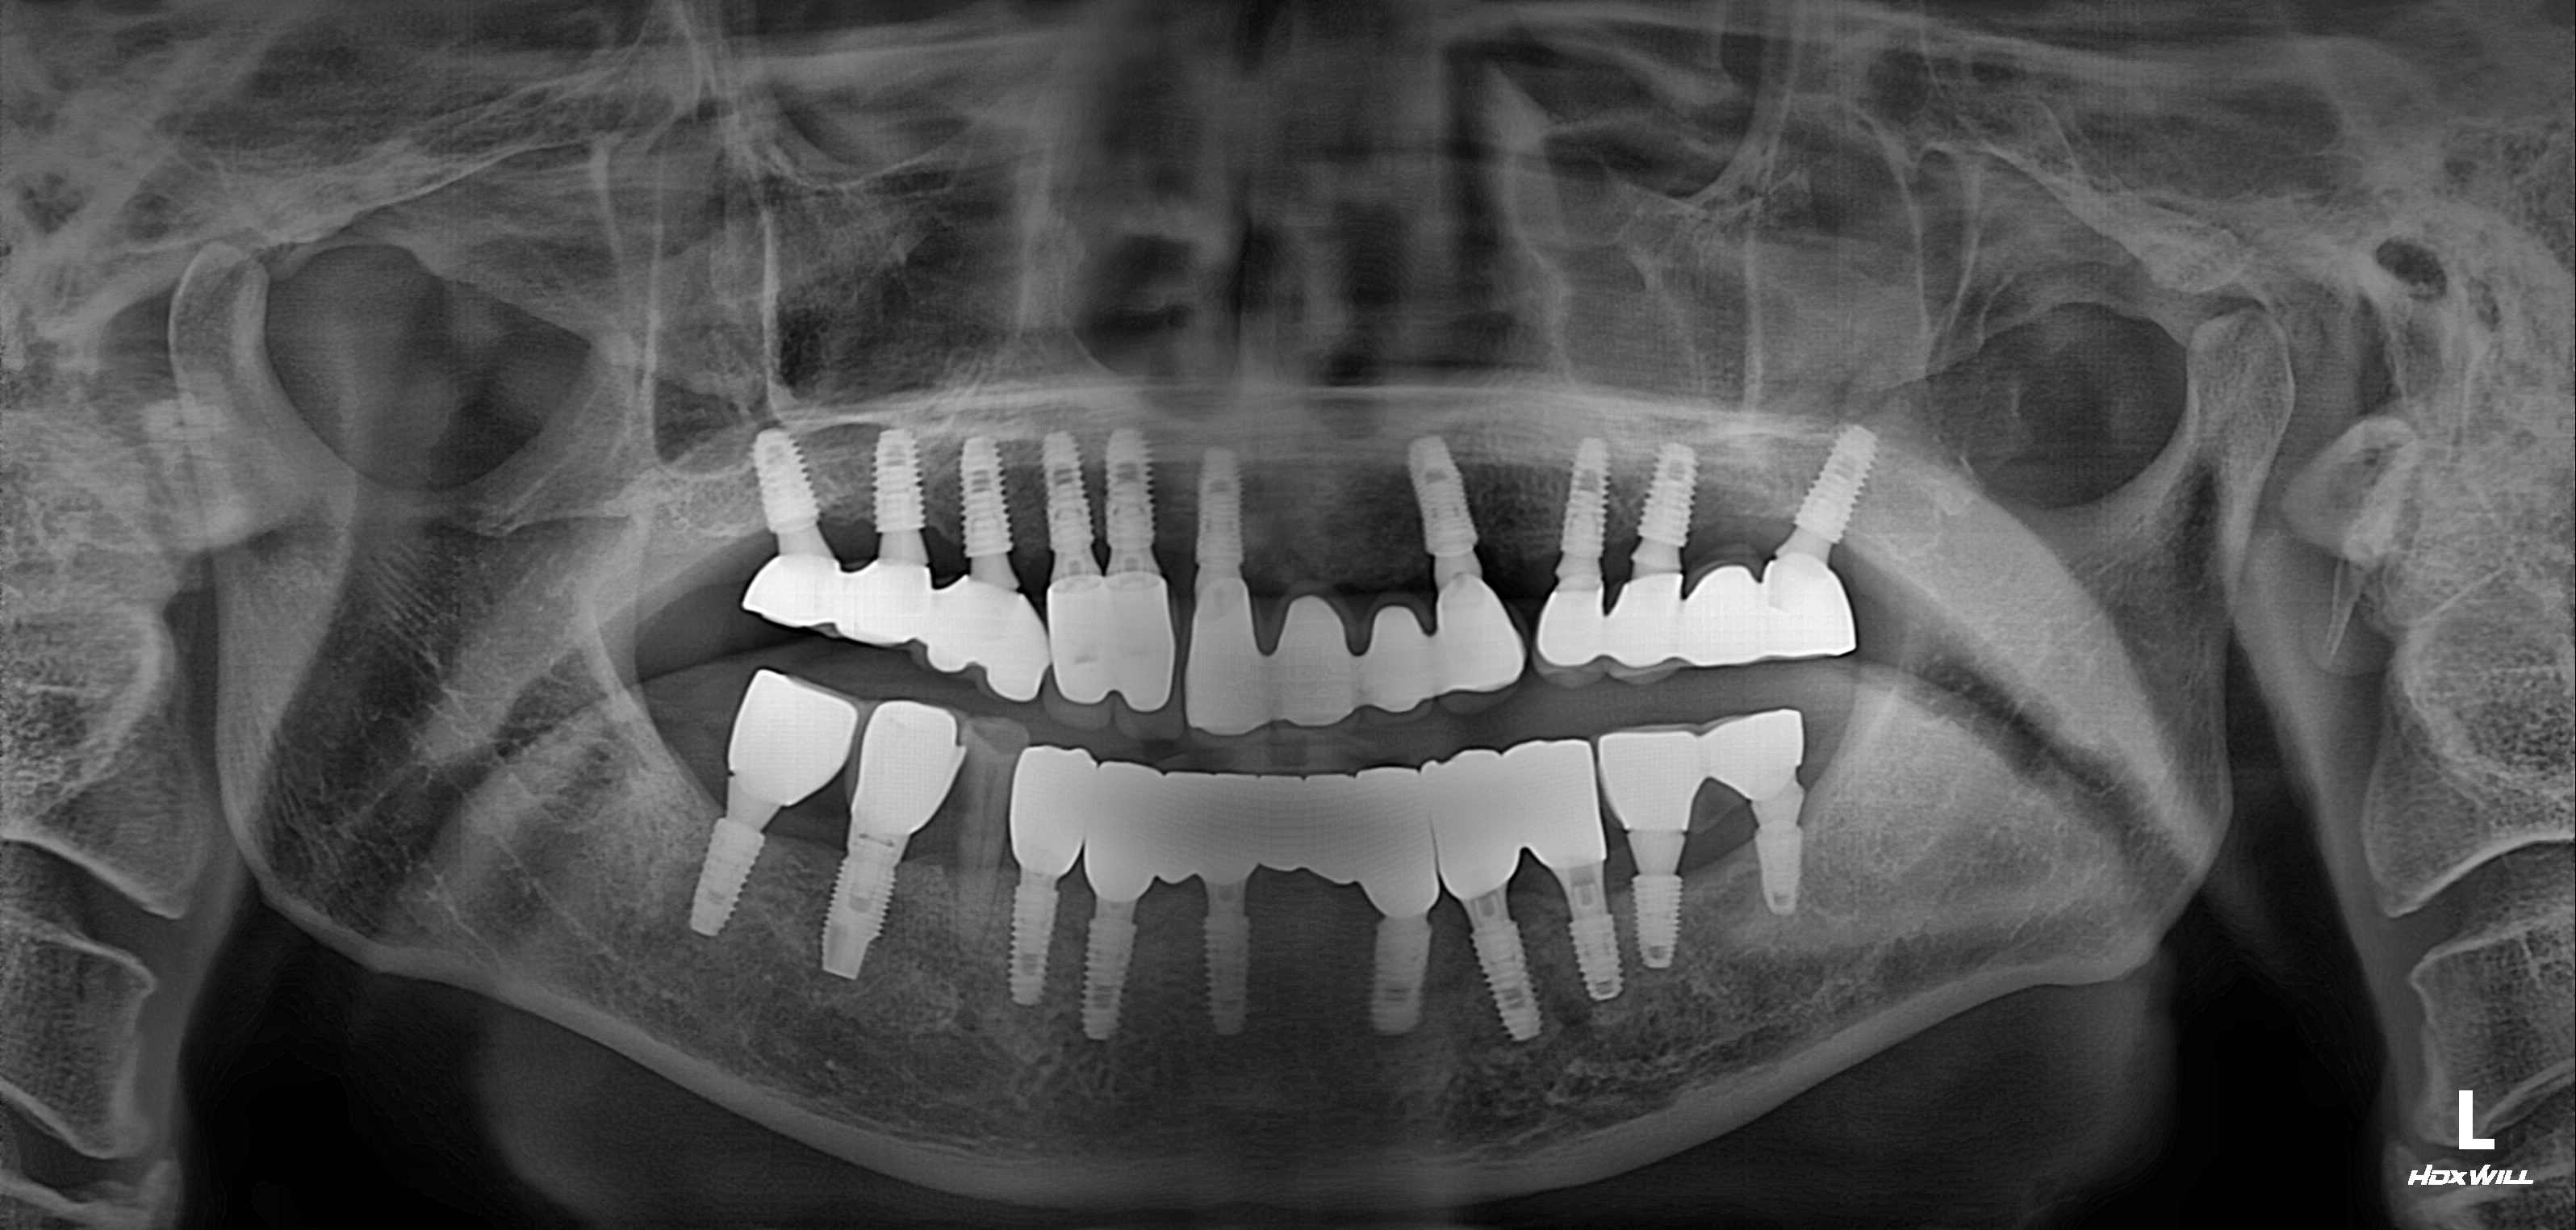

수술 전

수술 후

전악임플란트 식립사례

전후사진